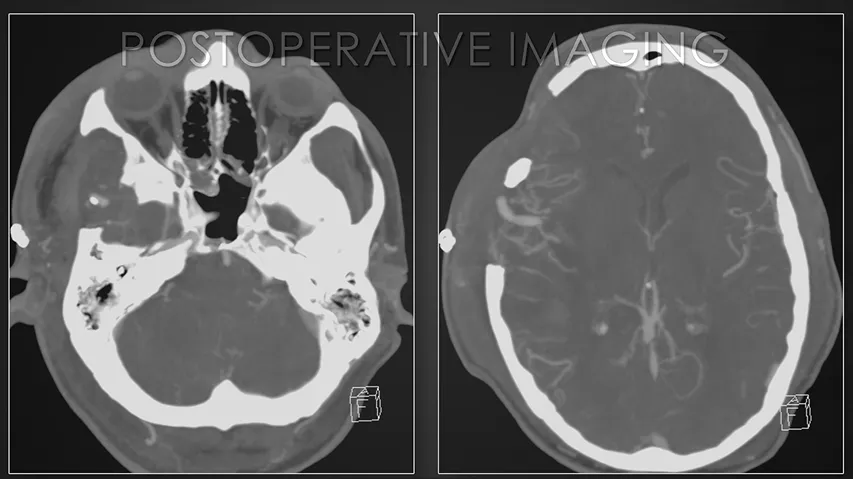

术后影像